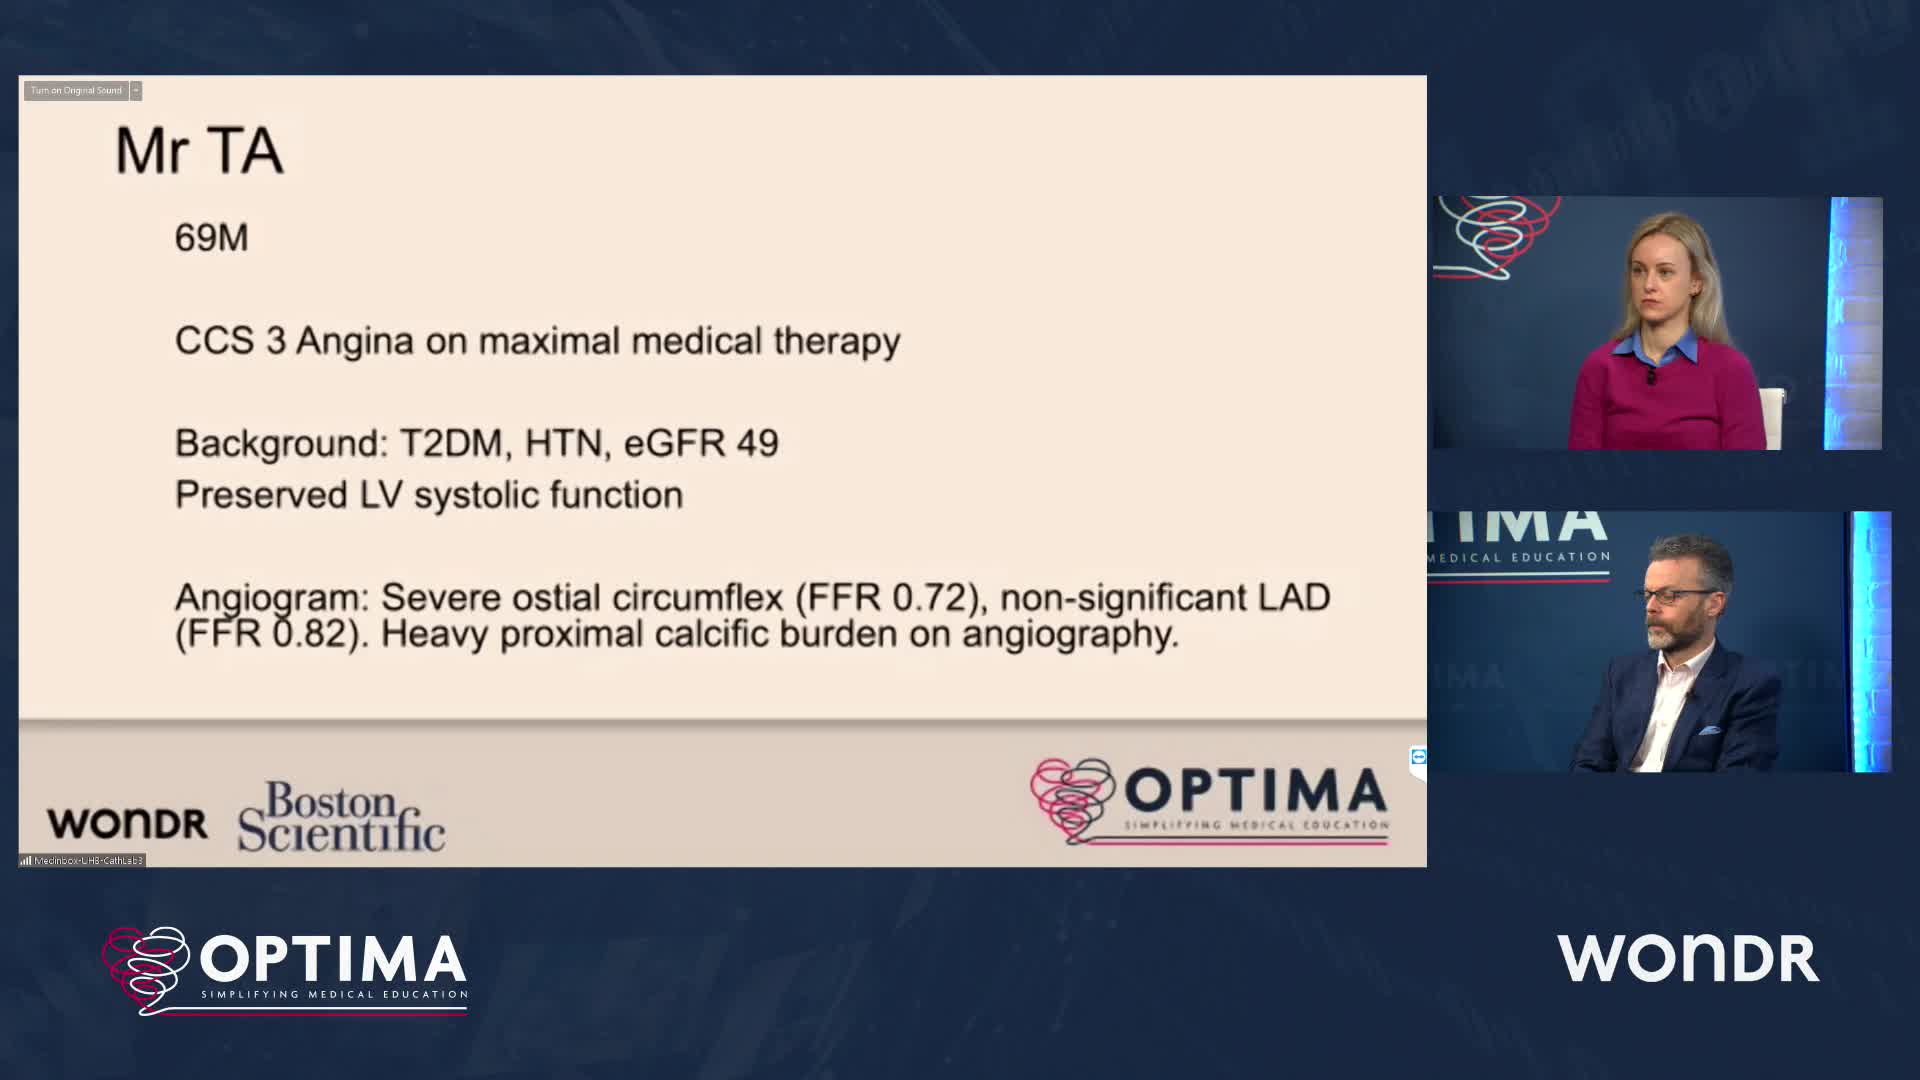

Calcium webinar with Boston Scientific

Treatment of coronary arterial calcium (CAC) has being redefined. We explore the interaction between CAC and patient...